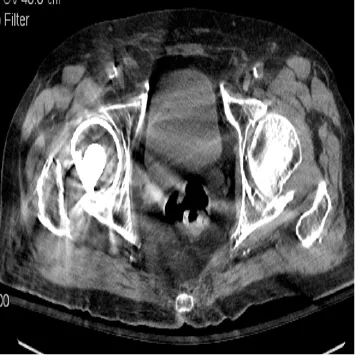

L’avancée la plus récente mais également la plus significative est l’introduction d’un nouveau type de reconstruction des images, la reconstruction itérative [7] : depuis la découverte de la technique du scanner par Sir Hounsfield, les images étaient reconstruites par rétroprojection filtrée. La reconstruction itérative est plus complexe sur le plan mathématique et était impossible à mettre en œuvre avant les progrès récents de l’informatique. La méthode consiste à reconstruire l’image par hypothèses successives appelées itérations. Il existe plusieurs techniques différentes selon les constructeurs. Toutes ces méthodes permettent de diminuer très significativement la dose délivrée au patient, puisqu’elles améliorent le rapport signal/bruit des images même celles initialement bruitées. L’ensemble des machines actuellement disponibles sur le marché proposent cette méthode et elle est donc utilisée de façon routinière sur les examens abdominaux. Ces méthodes permettent également de limiter les artéfacts métalliques (dit de renforcement de faisceaux) que l’on observait avec la reconstruction filtrée (Fig. 2) [8].

Figure 2. Comparaison de la même image reconstruite par rétroprojection filtrée (A) et par reconstruction itérative (B).

Les artéfacts liés à la prothèse de hanche sont diminués sur le mode itératif